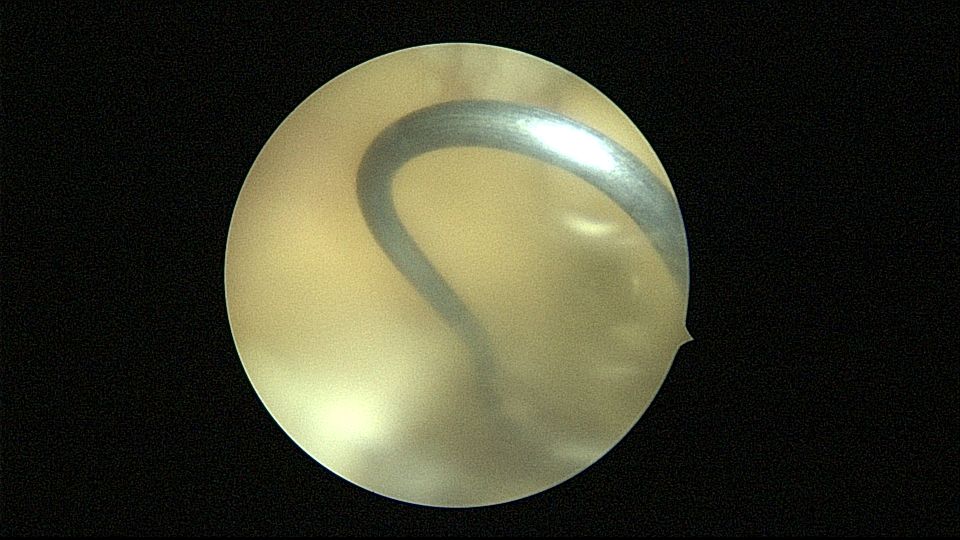

54岁,G2P1,顺产1次,安环16年,绝经10年,无不适症状,B超提示节育器嵌顿,宫腔积液2.3cm*1.9cm,血常规正常,白带常规乳酸杆菌少,其余指标正常。宫腔镜见宫颈管中上段封闭粘连,镜鞘分离粘连,见V型环一臂铜环全部嵌入右侧宫壁肌层内,取出节育器,宫腔内见灰白色脓液漂浮,膨宫液冲洗脓液,宫腔镜下无脓苔后结束手术,术后抗炎治疗。病检:宫腔少许宫内膜,呈慢性炎改变。